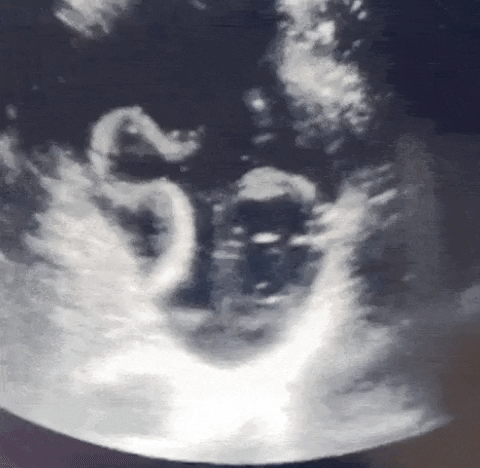

심지어 병원에서 검사를 하던 의사는 깜짝 놀라고 말았는데요. 그 이유가 바로 위장 속에 있던 큰 기생충이 살아서 움직이고 있었기 때문입니다. 기생충의 움직임이 초음파에 잡히는 등 의사도 처음 보는 일로 놀랐다고 합니다. 위장 속에서 살아서 움직이는 기생충을 봤다는 것은 충격 그 자체입니다.

병원에 찾았을 때 기생충의 여부는 초음파 검사를 통해 알 수 있고 위나 장에 기생충이 기생하여 살고 있을 때에는 반드시 알맞은 치료법으로 치료를 해야 하고 심한 경우에 수술을 진행할 수도 있습니다.